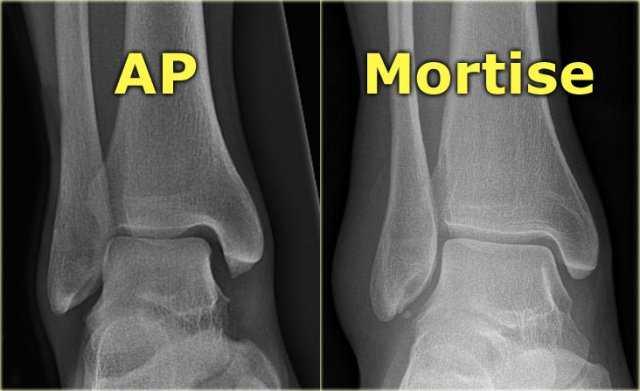

Mortise view

A basic radiographic examination of the injured ankle consists of an AP-view, a Mortise-view and a lateral view.

The Mortise-view is an AP-view taken with a 15-25? endorotation of the foot.

The technologist turns the foot inwards until the lateral malleolus is at the same height as the medial malleolus.

This view visualizes both the lateral and medial joint spaces.

On a true AP-view the talus overlaps a portion of the lateral malleolus, obscuring the lateral aspect of the ankle joint.